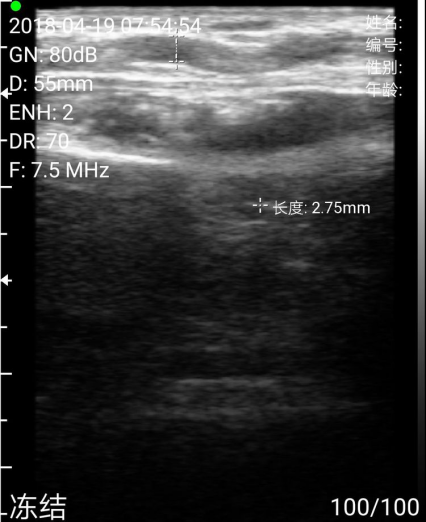

测量尺动脉直径(这里尺动脉有一个迂曲,术中有一点儿麻烦)

测量贵要静脉直径如图。均在满意范围,遂决定行右上肢尺动脉贵要静脉内瘘成形术。